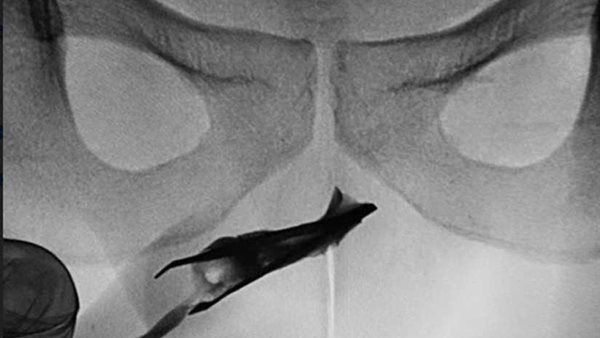

وقام الأطباء ببذل جهود مضنية لإزالة "الملقاط" بالضغطً على جانبي القضيب لإخراج الملقاط الذى يبلغ حجمه 2.7 بوصة